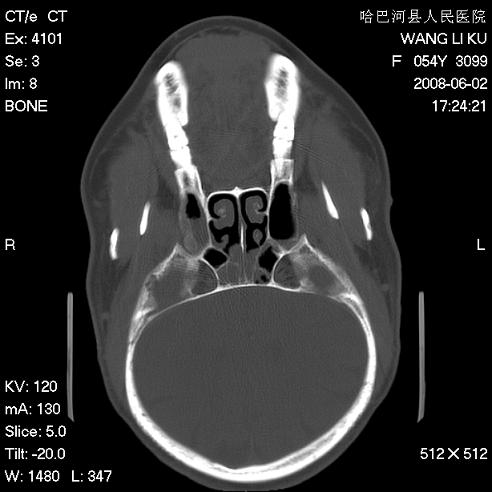

标题: CT13803:反复性鼻塞、流涕一年余 [打印本页]

标题: CT13803:反复性鼻塞、流涕一年余

副鼻窦炎,右上额窦积脓。左眼肌锥内见致密影,视神經受压

1.全组副鼻窦炎2.双侧上颌窦积液

1)全副鼻窦炎(左侧上颌窦黏膜下囊肿或息肉)。2)左眼眶肌锥内不规则小结节状软组织密度影;考虑为小血管瘤可能。建议行ct增强扫描检查。

全组副鼻窦炎,左侧肌锥内不规则形软组织肿块影,与眼外肌密度相当,左侧视神经受压,肿块与视神经及眼外肌分界清晰,眼外肌无增粗,眶壁无破坏,球后脂肪间隙不模糊,考虑良性改变,小血管瘤或神经源性肿瘤可能,建议增强扫描。

谢谢,增强扫描做了,眶内病灶与海绵窦同步明显强化,血管瘤